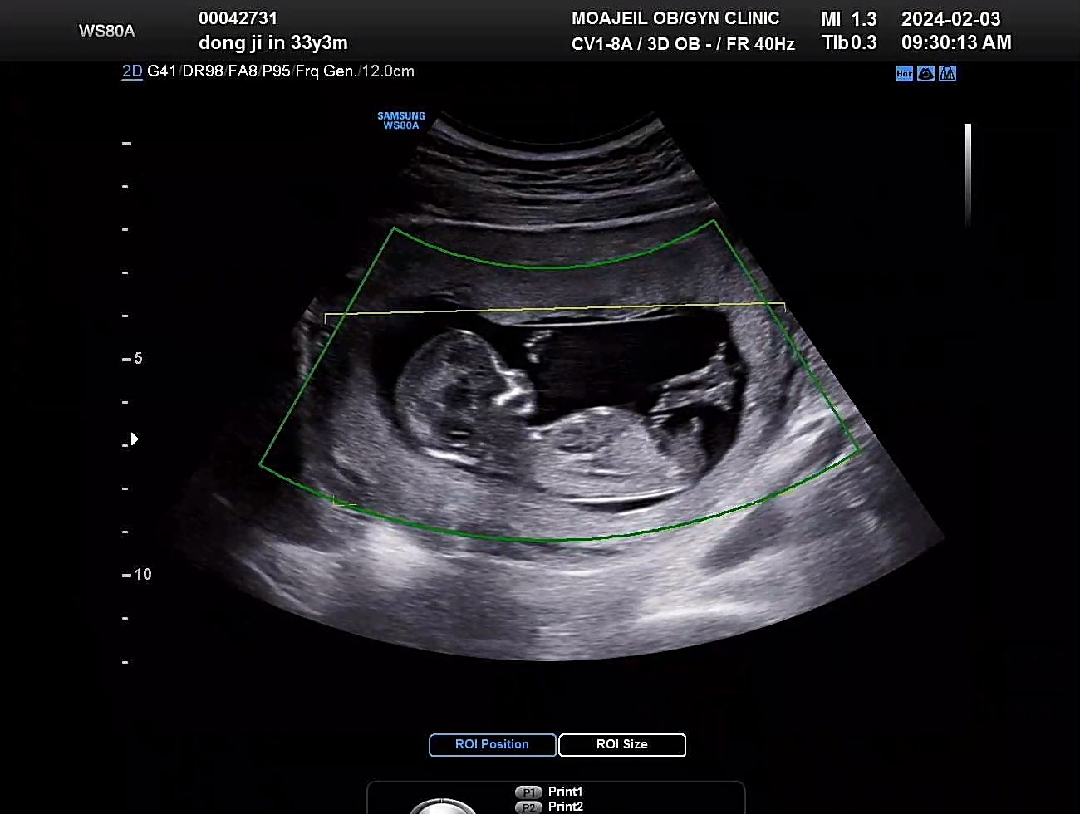

13주 각도법 봐주세요ㅠㅠ 넘 궁금해요

각도법 봐주세요~~~~!!!

아들같아요